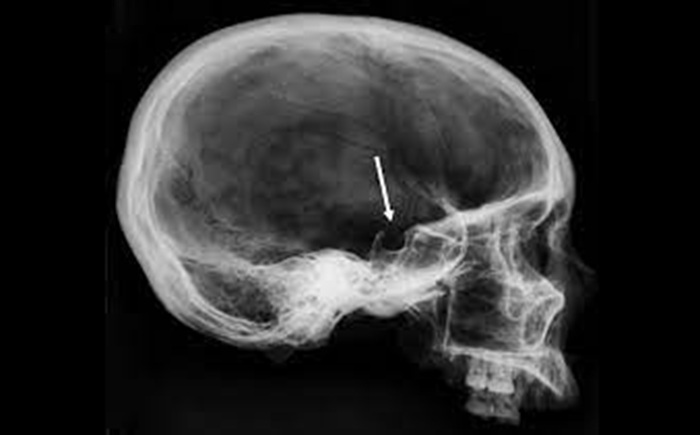

Рентген гипофиза визуализирует форму, структуру органа и его габариты. Также в ходе выполнения данной процедуры можно увидеть опухоли, новообразования, атрофию стенок, остеопороз или утончение клиновидных отростков, нечеткое выражение контуров.

Описание результатов рентгена гипофиза

Описывает полученные снимки рентгенолог в течении рабочего дня. Если на снимке наблюдается опухоль, специалист опишет ее размеры, локализацию, структуру и форму. На следующий день пациент может их забрать или их передадут лечащему врачу для установления диагноза на основе индивидуальных особенностей обследуемого.